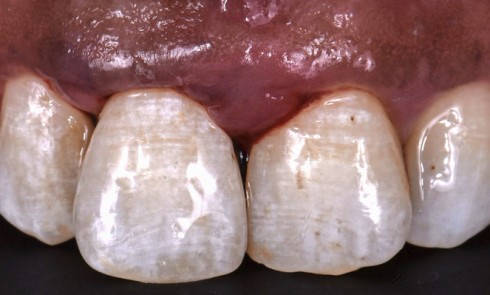

Grand Prix éditorial ID 2023, L’implantologie numérique, maintenant et demain 1er cas lauréat 2023   Objectif thérapeutique Une patiente de...

Endodontie

Article réservé à nos abonnés Nécrose pulpaire et fêlure, quelle stratégie clinique ?